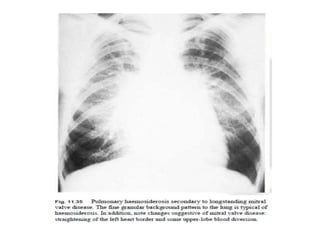

• longstanding pulmonary venous hypertension

and thus chronic features: Haemosiderosis

and pulmonary ossific nodules may

occasionally be seen.